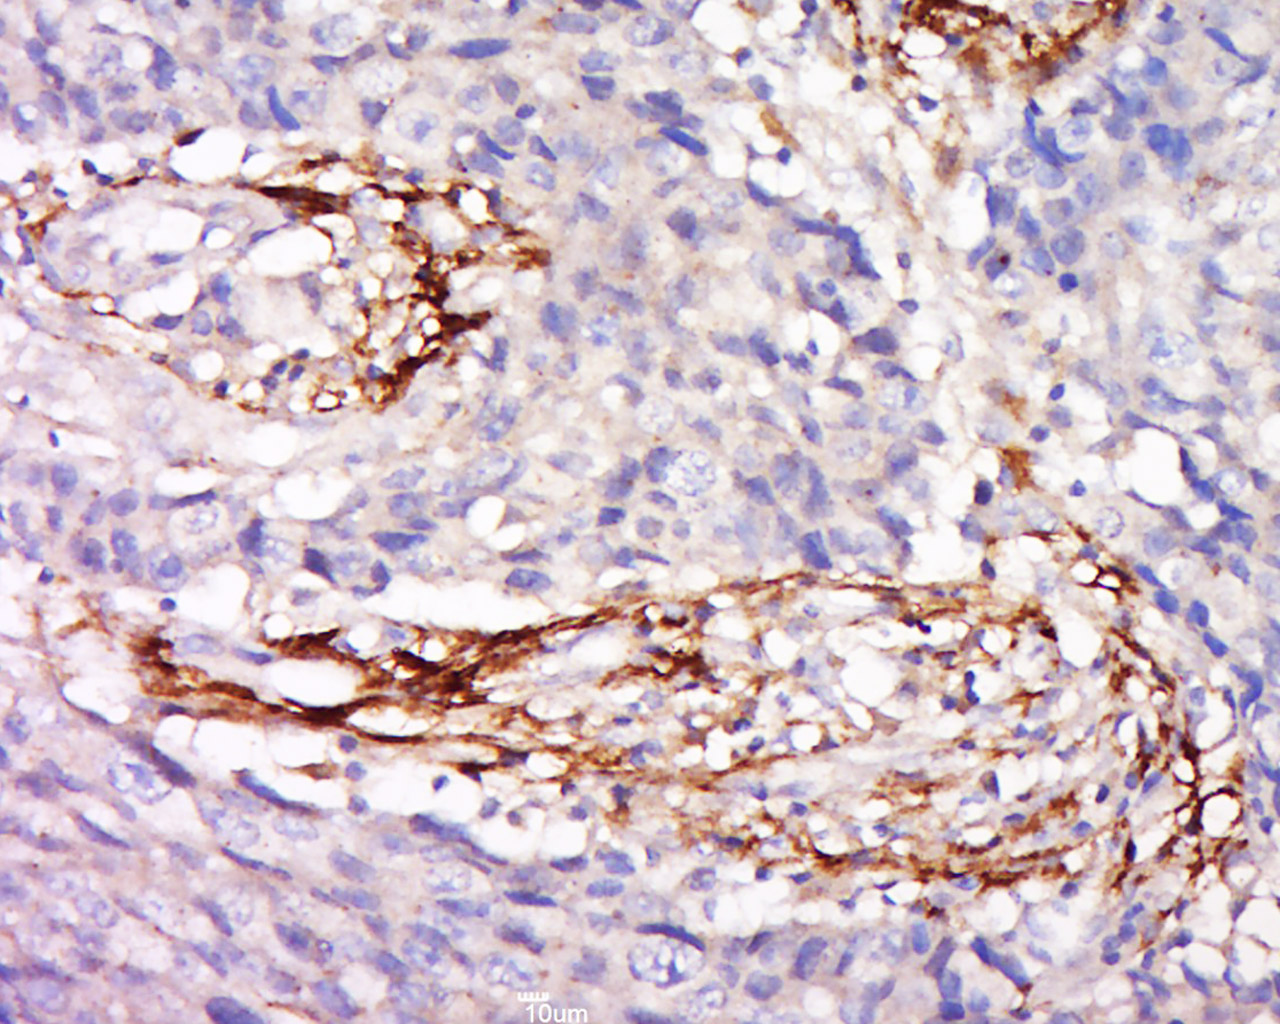

Tissue/cell: Human colon carcinoma; 4% Paraformaldehyde-fixed and paraffin-embedded; Antigen retrieval: citrate buffer ( 0.01M, pH 6.0 ), Boiling bathing for 15min; Block endogenous peroxidase by 3% Hydrogen peroxide for 30min; Blocking buffer (normal goat serum,C-0005) at 37℃ for 20 min; Incubation: Anti-ZA2G Polyclonal Antibody, Unconjugated(bs-19382R) 1:500, overnight at 4°C, followed by conjugation to the secondary antibody(SP-0023) and DAB(C-0010) staining